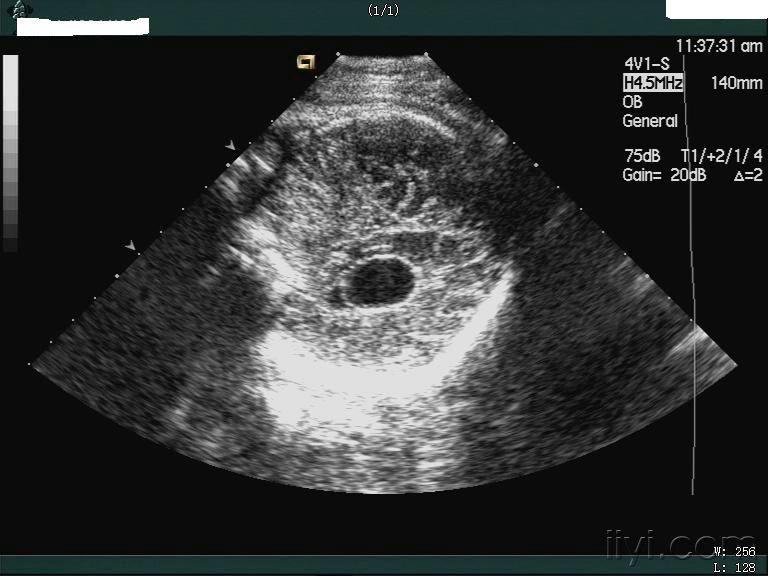

【产科超声】脉络丛囊肿的超声诊断

图片尺寸640x479

超声入门贴979中孕胎儿脉络丛囊肿

图片尺寸560x420